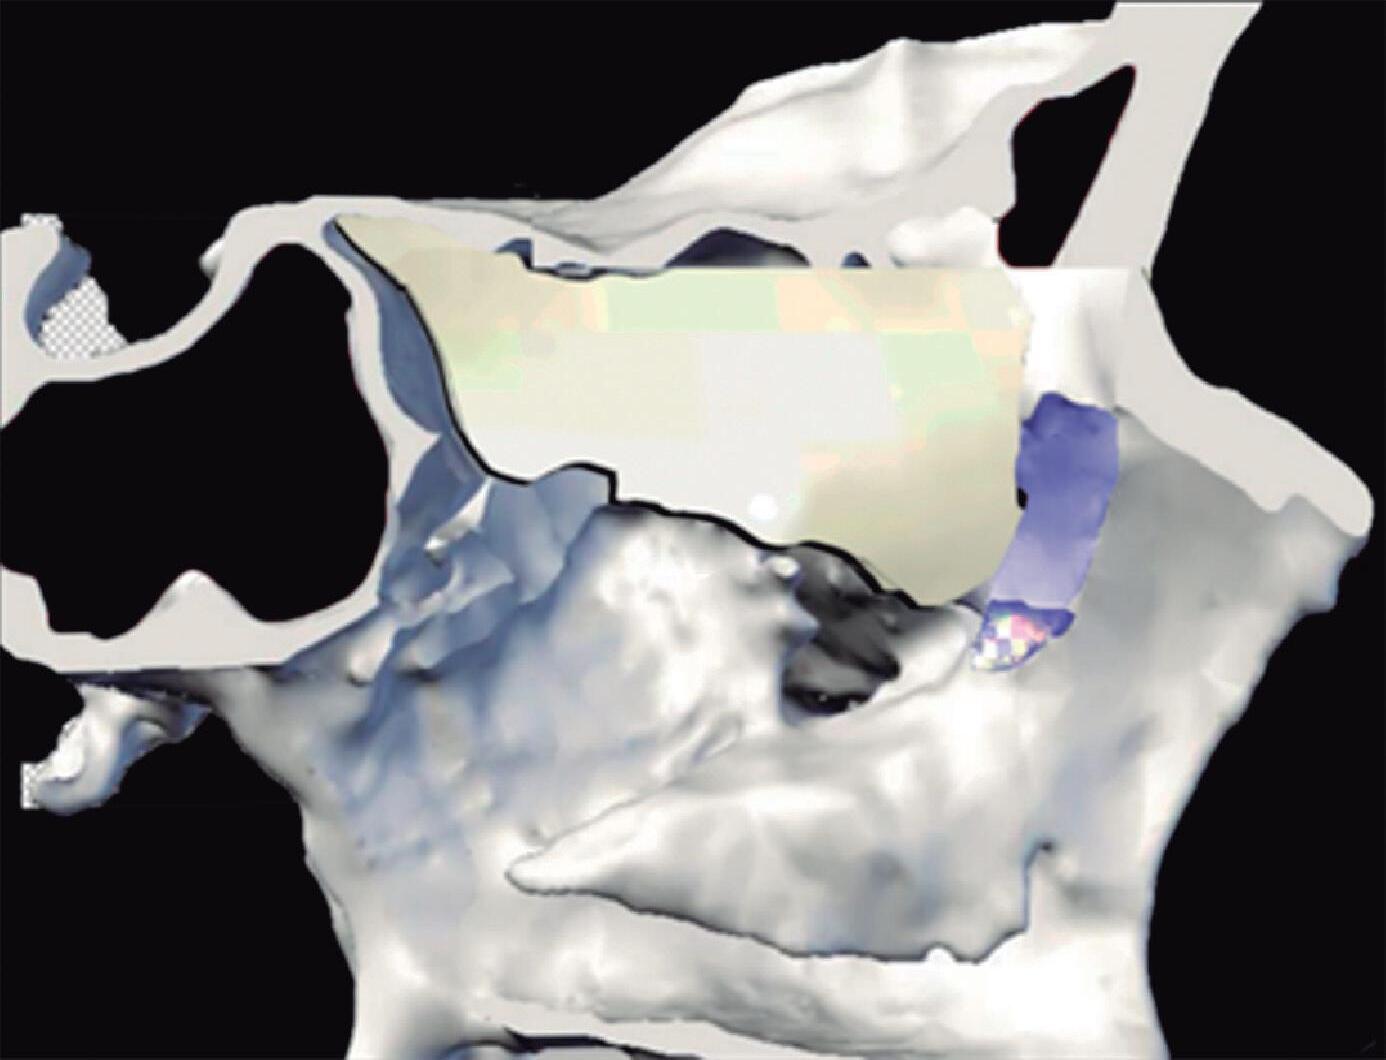

Fig. 1-20. Reconstrução tridimensional de TC demonstrando a lamela basal situada posteriormente à bulha etmoidal, acoplada à parede medial da órbita, fechando a câmara anterior: verde – concha média; vermelho – bulha etmoidal; amarelo – parede medial da órbita; lilás – processo uncinado.

A placa das conchas, juntamente com a concha média, é mantida arquitetonicamente estável por lamelas ósseas (lamelas basais da concha média e superior) que vão terminar na parede medial da órbita e no piso da fossa anterior.

Lamela Basal Porção oblíqua que parte da face meatal da concha média e se insere na lâmina papirácea e base do crânio. É a parede posterior do meato médio, ou o limite posterior da câmara anterior.

Fig. 1-45. Limites do seio etmoidal: (1) Limite anterior: junção da placa do agger nasi com o processo frontal do maxilar; (2) limite posterior: parede anterior do seio esfenoidal; (3) limite lateral: processo frontal do maxilar mais anteriormente, osso lacrimal (unguis) e a parede medial da orbita (lâmina papirácea) posteriormente; (4) limite superior: piso da fossa anterior, composto anteriormente pela parte medial do processo orbital do osso frontal e posteriormente pelo plano esfenoidal; (5) limite medial: estrutura vertical da concha média; (6) limite inferior: o seio etmoidal comunica-se livremente com a fossa nasal.